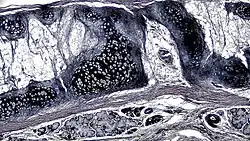

![]() A cross section of mammalian elastic cartilage | |

Elastic cartilage is histologically similar to hyaline cartilage but contains many yellow elastic fibers lying in a solid matrix. These fibers form bundles that appear dark under a microscope. The elastic fibers require special staining since when it is stained using haematoxylin and eosin (H&E) stain it appears the same as hyaline cartilage.[3] Verhoeff van Geison stains are used (giving the elastic fibers a black color), but aldehyde fuchsin stains, Weigert's elastic stains, and orcein stains also work.[3] These fibers give elastic cartilage great flexibility so that it is able to withstand repeated bending. Similarly to hyaline one or multiple chondrocytes lie between the spaces (or lacunea) in the fibres.[2] The chondrocytes only make up 2% of the tissue's volume.[2] Chondrocytes and the extracellular matrix are contained in an outerlayer named the perichondrium[2] (which is a layer of dense irregular connective tissue that surrounds cartilage which is independent of the joint).[3] It is found in the epiglottis (part of the larynx), and the pinnae (the external ear flaps of many mammals). Elastin fibers stain dark purple/black with Verhoeff's stain.